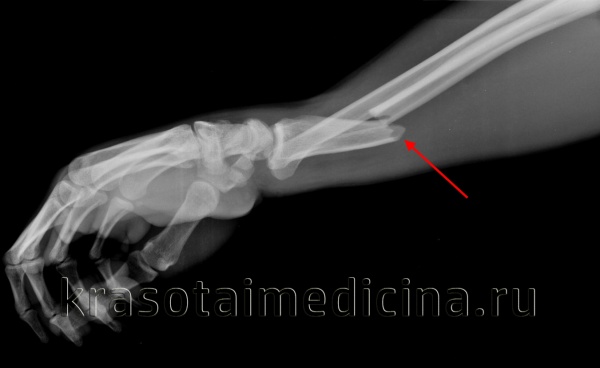

Рентгенография лучезапястного сустава. Перелом дистального метаэпифиза лучевой кости со смещением отломков.

Повреждение сопровождается резкой болью, отеком и кровоизлияниями. Возможна крепитация и патологическая подвижность. При смещении выявляется видимая деформация чуть выше сустава или в его проекции. Движения и пальпация резко болезненны. Диагноз подтверждают по результатам рентгенографии лучезапястного сустава. При сложных переломах и в ходе предоперационной подготовки может потребоваться проведение КТ лучезапястного сустава и МРТ. Лечение в подавляющем большинстве случаев консервативное.

Переломы лучевой кости в типичном месте (чуть выше лучезапястного сустава) – самые распространенные переломы костей предплечья. Нередко наблюдаются у детей и у молодых людей, однако, чаще всего встречаются у лиц пожилого возраста, что обусловлено остеопорозом. Как правило, возникают при падении с опорой на вытянутую руку, могут сопровождаться или не сопровождаться смещением фрагментов. С учетом характера смещения выделяют две разновидности таких повреждений – переломы Коллеса и переломы Смита. При переломе Коллеса дистальный отломок смещается к тылу, при переломе Смита – к ладони. Кроме того, такие переломы могут быть внутрисуставными или внесуставными, открытыми или закрытыми.